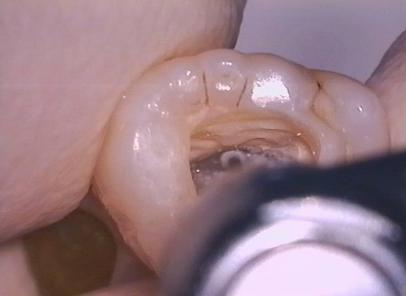

Om snel, gemakkelijk en veilig toegang tot de pulpakamer te verkrijgen is het verstandig om een niet te lange diamantboor te gebruiken. Zo wordt voorkomen dat per ongeluk door de bodem van de pulpakamer kan worden geboord. Vrijwel altijd kan worden volstaan met een kopsnijdende diamantboor om de pulpakamer te openen. In de richting van de pulpahoorn van het grootste kanaal. Vervolgens wordt met een wat langere diamantboor het volledige dak van de pulpakamer verwijderd. Hiervoor is de Endo Access bur (kopsnijdend) en de Diamendo (diamant, niet kopsnijdend) of de EndoZ (hardstaal, niet kopsnijdend) zeer geschikt.

Nu wordt met LN boren (hebben een lange schacht en men kan er dus gemakkelijk langs kijken)de monding van de kanalen vrij geprepareerd.

LN boren zijn ook bijzonder geschikt om de kanaalingang van MB2 te vinden. Op basis van een “wit puntje”, wat bestaat uit dentineslijpsel in het kleine kanaaltje, kan vrijwel zonder gevaar een aantal millimeters naar apicaal worden geboord. Vervolgens is dan met een dunne vijl wel doorgang in het kanaal te verkrijgen. Uiteraard is dit zonder de behandelmicroscoop niet te doen!